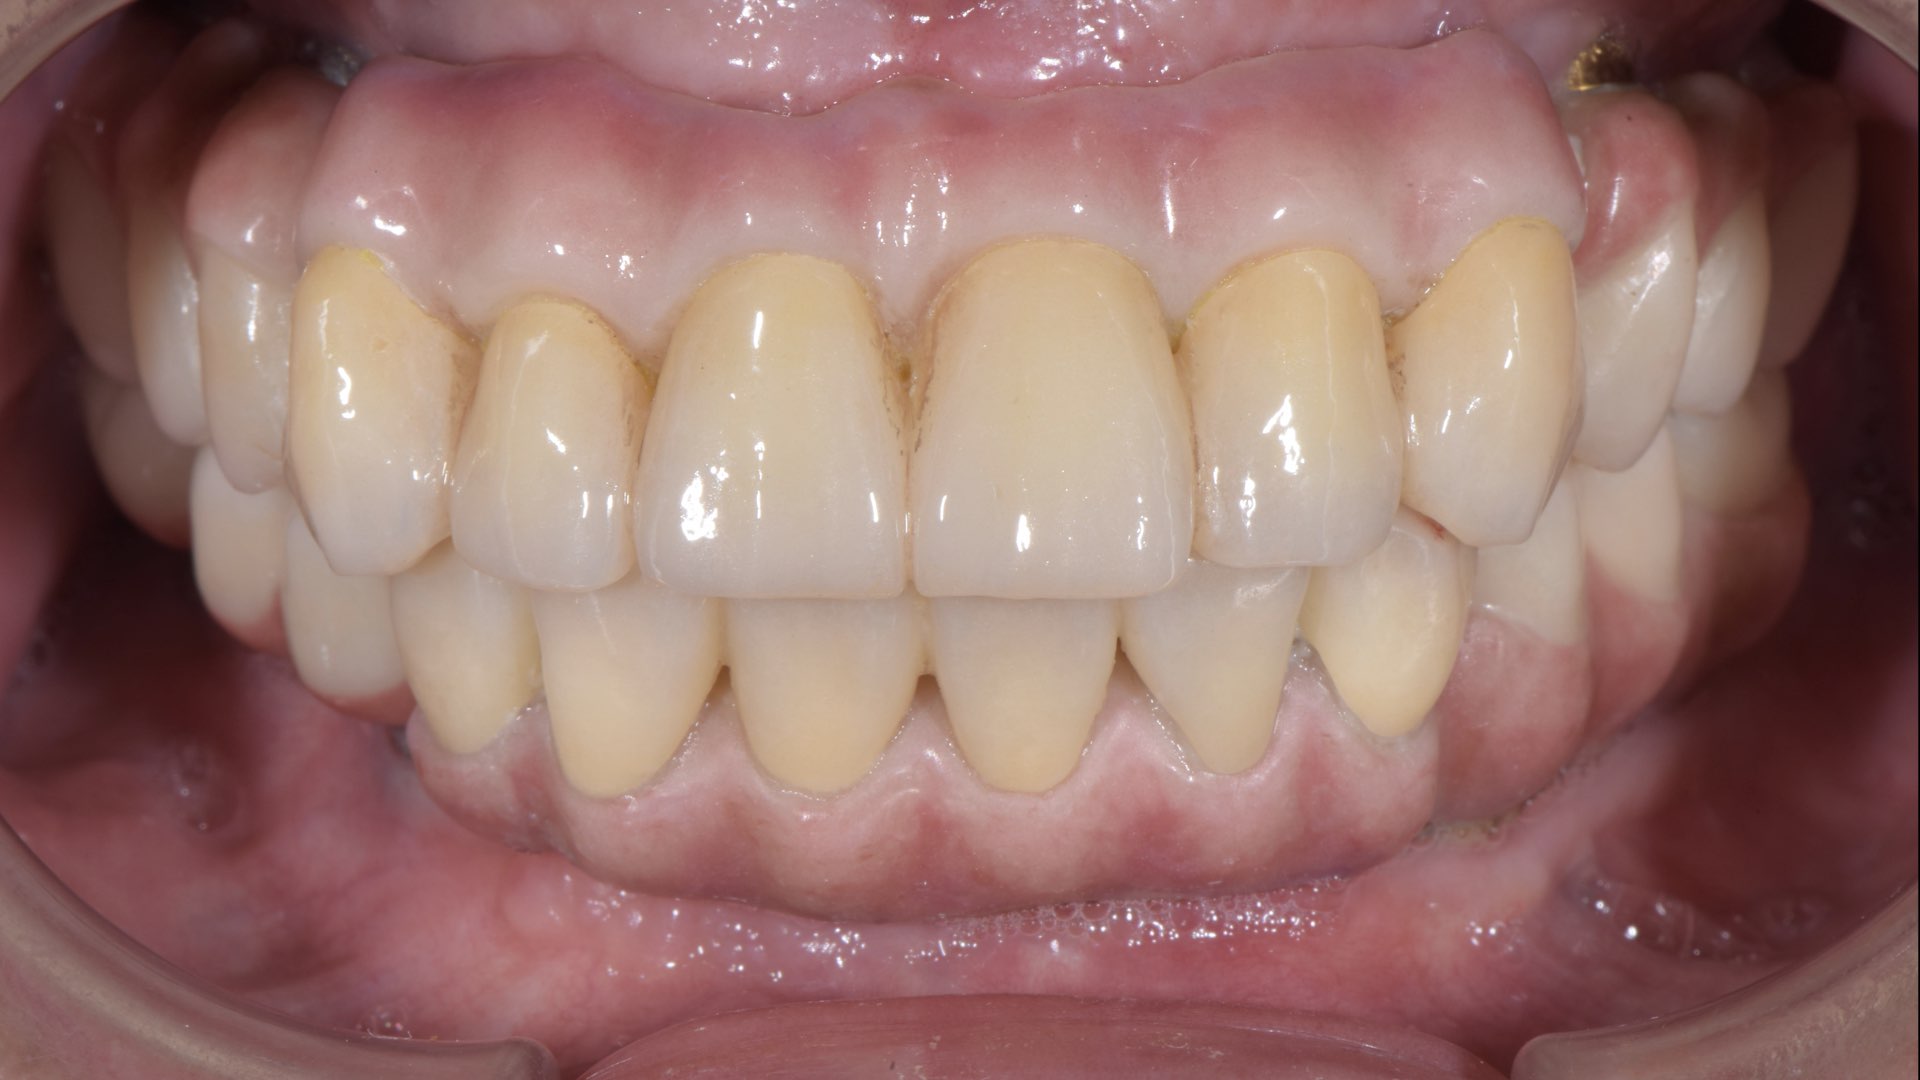

全口植牙固定義齒